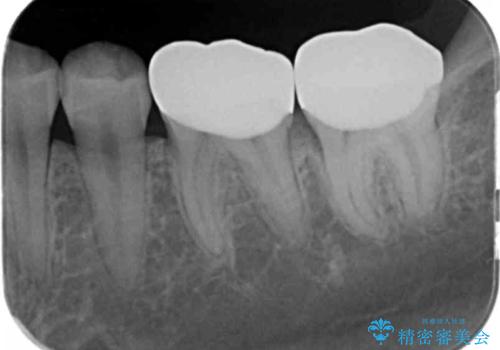

変色した樹脂の詰め物 セラミックでのやり替え

奥歯が樹脂の詰め物で継ぎ接ぎになっていることが確認されたため、今後の虫歯リスクを減らすために適合の良いフルジルコニアクラウンを入れていきます。

樹脂で継ぎ接ぎになった歯はそうでない歯と比べて虫歯になるリスクが高いです。

樹脂をすべて取り、虫歯も取り切った後に適合の良いクラウンを装着することで今後の虫歯リスクを減らすことができます。